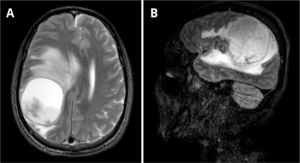

A 58-year-old male recycling worker was admitted to the emergency department with sudden-onset left-sided hemiparesis and altered mental status, prompting an initial evaluation for acute stroke. The patient also had a one-year history of progressive cognitive impairment, confusion, behavioral changes, and weight loss, with a BMI of 16.45 kg/m2 upon admission. Brain magnetic resonance imaging revealed a large intra-axial expansile lesion centered in the right parietal lobe, predominantly cystic and necrotic in appearance, containing fluid-fluid levels and a diffusion restriction component in its posterior aspect, suggestive of an abscess (Fig. 1).

Axial T2-weighted MRI (A) shows a lesion measuring 5.9 × 5.4 × 5.4 cm (CC × LL × AP) and exerts a compressive effect on the brain parenchyma, with hyperintense areas in the white matter secondary to vasogenic edema, accompanied by subfalcine herniation and right uncal herniation into the suprasellar cistern. There is an approximate 1.7 cm midline shift to the left. Peripheral rim enhancement without surrounding capsule irregularity is observed, findings that are suggestive of a tuberculous abscess rather than a pyogenic one. Sagittal MRI on T1 complements the visualization of the lesion (B).